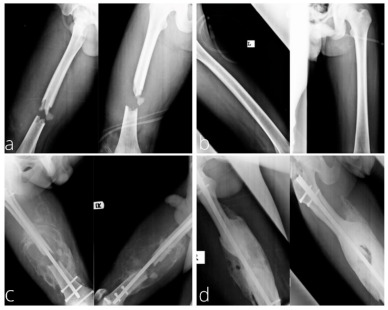

Premature Epiphyseal Closure (B) - Exuberant callus formation – typically temporary – will be remodelled to become a more typical bone shape

Exuberant callus formation - Osteoarthritis due to damage affecting ends of long bones – within joint space